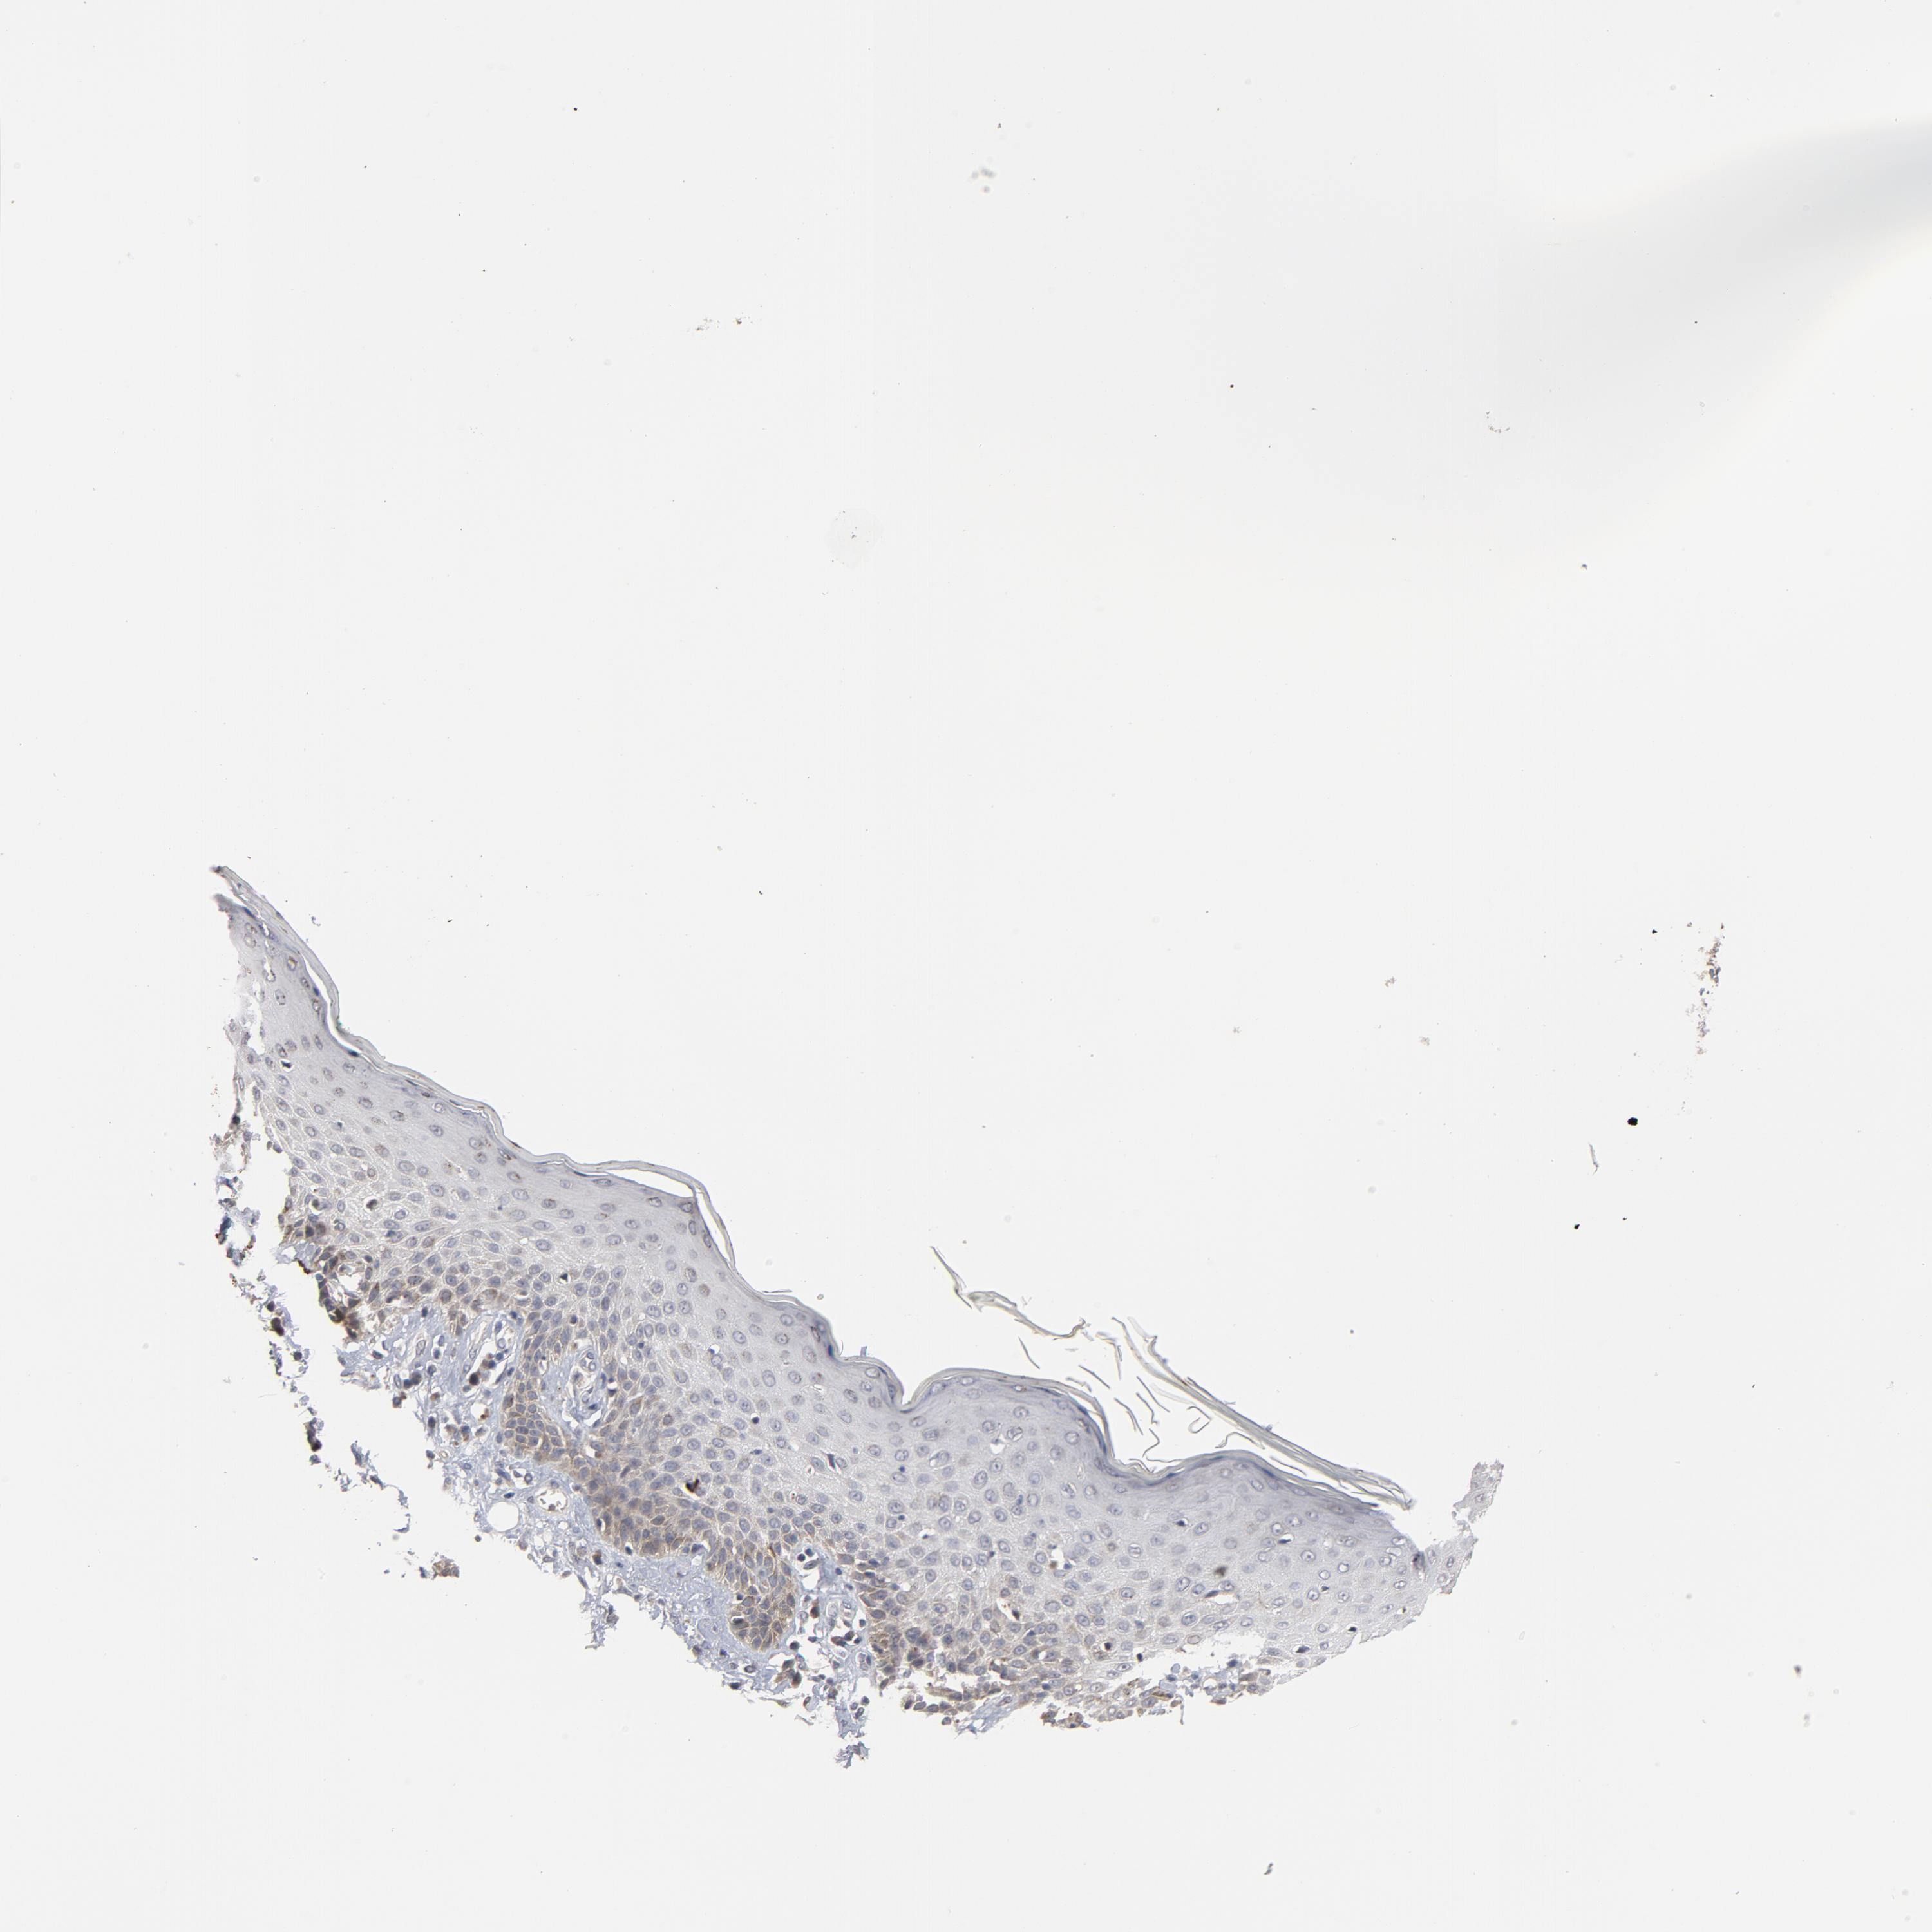

SKIN CANCER - Protein expressioni

A mouse-over function shows sample information and annotation data. Click on an image to view it in a full screen mode. Samples can be filtered based on level of antibody staining by selecting one or several of the following categories: high, medium, low and not detected. The assay and annotation is described here.

Each image is clickable and will lead to virtual microscopy that enables deeper exploration of all samples and also displays staining intensity scores, fraction scores and subcellular localization as well as patient and tissue information for each sample.

Antibody HPA048630

Antibody HPA061142

Antibody CAB004026

Staining

High

Medium

Low

Not detected

Intensity

Strong

Moderate

Weak

Negative

Quantity

>75%

75%-25%

<25%

None

Location

Nuclear

Cytoplasmic/membranous

Cytoplasmic/membranous,nuclear

Basal cell carcinoma

Squamous cell carcinoma, NOS